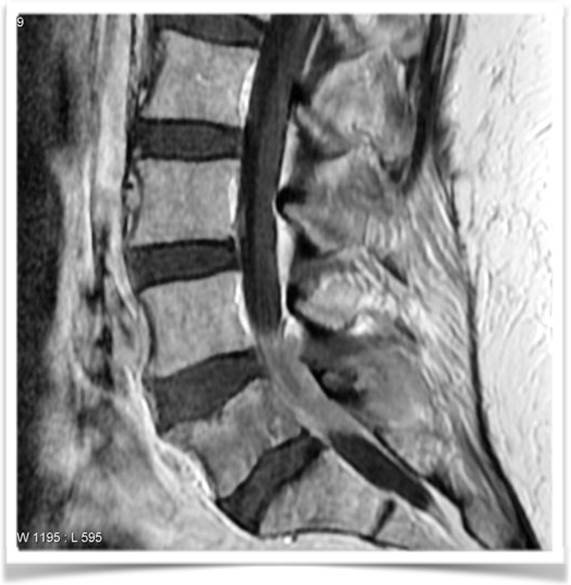

Spine cages are implants for levelling and relieving the pressure on the spine. These implants are minimally invasive normally used in conjunction with screws made of Titanium in patients with problems caused spinal instability stenosis or many others spinal degenerative diseases. The cages themselves are made of PEEK (polyetheretherketone), a highly biocompatible material, even for allergy sufferers. In the past, these cages were manufactured conventionally in titanium, with the result being that, in some cases, the titanium component had a negative impact on the bone structure due to the rigidity of the cage realized by drilling with a very hard structure. This was caused by the implant's significantly lower elasticity versus the bone. One alternative is PEEK, a high-performance plastic with compression properties or elasticity (E-module) rivalling that of bone. In addition, PEEK components cause no artefacts in MRI (magnetic resonance imaging) and are thus easy to locate by the surgeon through imaging. One of the disadvantages of PEEK spine cages is their inability to be integrated into the bone structure and their eventual should slip off from the original position also after longer periods of implant. Polyetheretherketone is a high temperature resistant thermoplastic and belongs to the group of polyaryletherketones. Its melting temperature is 335°C.

The LaserCUSING additive laser melting method combines the strengths – and eliminates the weaknesses – of traditional titanium or PEEK components for spine cage applications. A laser-melted component can now offer the biocompatibility of titanium with the desired elasticity of a plastic material in a single product. Laser-melted spine cages have a very complicate geometry and not require to be re-treated (images 1a, b and c) to ensure an optimal surface structure. The highlight of this solution: its geometry, with partially different density distributions (embedded web-like structures), now gives titanium parts the same elasticity as a PEEK solution. Laser-melted cages can also be affordably manufactured in various dimensions depending on the anatomy of the patient, allowing for customised manufacturing. According to CEO Stefano Caselli, laser-melted cages represent "a true innovation that combines material-specific advantages such as biocompatibility, i.e., the ability to embed the material into the bone structure, and elasticity that is customised for the human body in a single product" (image 2). Surgeons can easily locate the cages using CT or MRI imaging. Laser melting also allows custom or small-series manufacturing, including "made-to-order" cages for patients with special anatomical conditions or standard solutions for other patients. A clinical study conducted in March 2014 in cooperation with Carl von Ossietzky University in Oldenburg, Germany, confirmed an excellent healing prognosis with these implants. (*Oldenburg study)